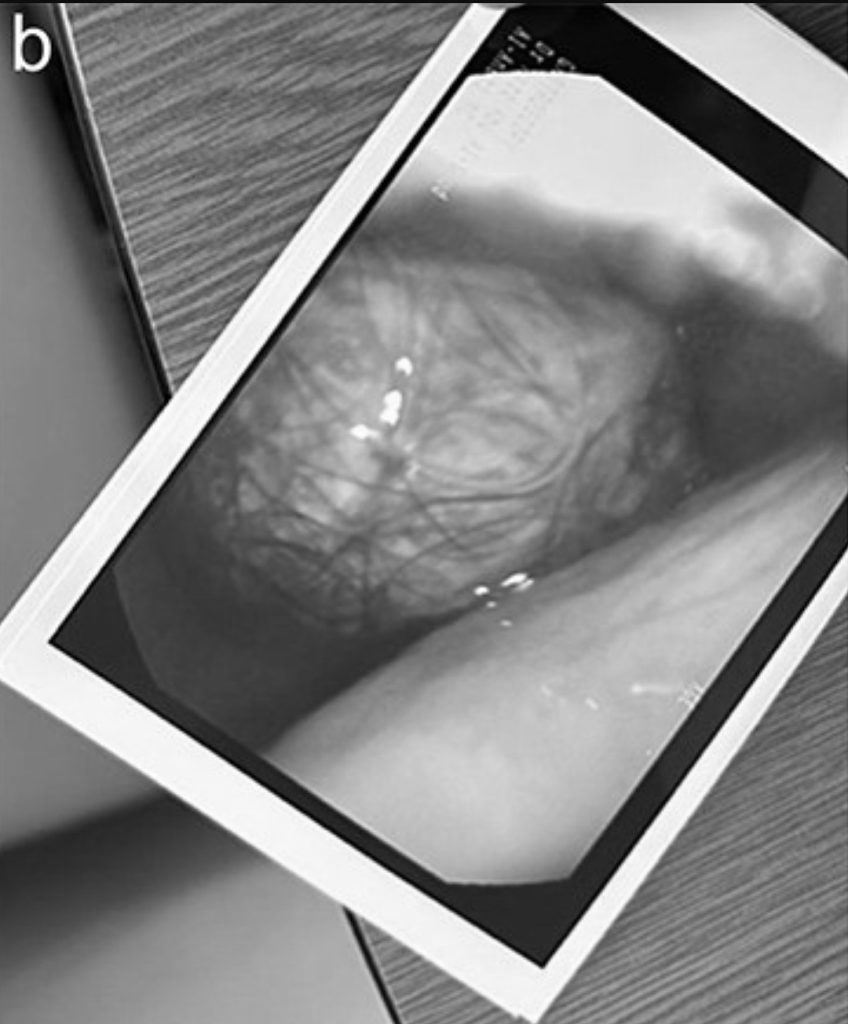

Do kích thước của khối tóc, việc loại bỏ bằng phương pháp nội soi là không thể nên nữ bệnh nhân đã phải trải qua phẫu thuật mở dưới gây mê toàn thân.

Búi tóc lớn được lấy ra cẩn thận và vẫn còn nguyên vẹn. Và sau 3 giờ đồng hồ, dị vật đã được lấy ra an toàn.